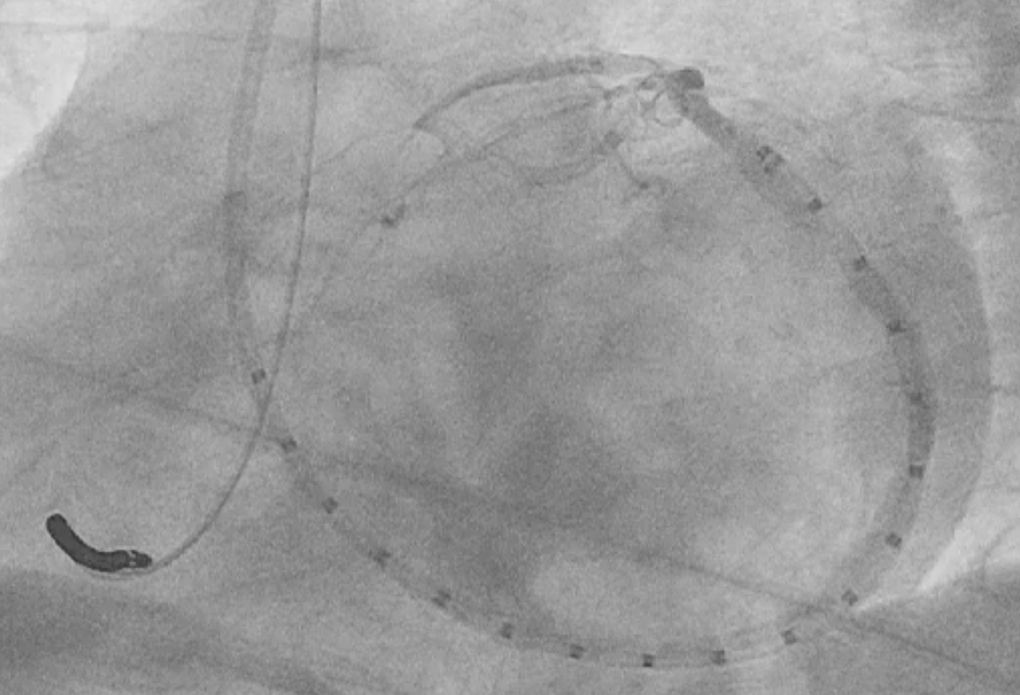

Sofern die Anatomie und die Indikationsstellung es anbieten, kann die Mitralklappeninsuffizienz auch über das sog. Carillon-Device interventionell erfolgreich behandelt werden. Hierbei wird, angelehnt an die chirurgische Mitralklappenrekonstruktion, der Mitralklappenring durch Einbringen eines Bandes/ Drahtkonstruktion verkleinert und so die Undichtigkeit verringert.